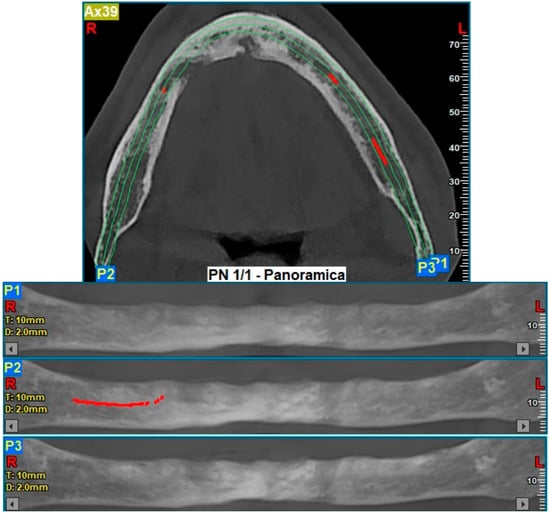

2. Case Description